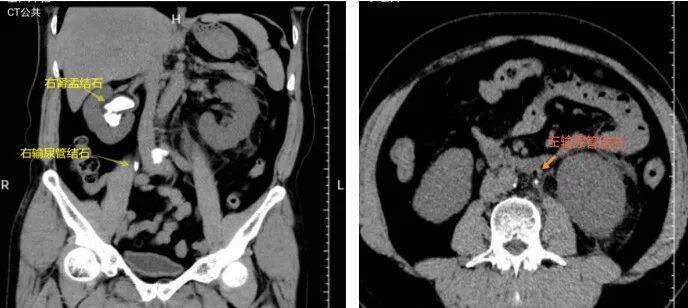

患者宋先生1月前因腰腹痛急诊入院,检查发现双侧输尿管上段结石、双肾结石伴肾盂积水,其中右肾结石为约4cm×3cm×2cm铸型结石,同时合并急性肾功能不全、肾积脓感染,病情危急,随时可能进展为急性肾衰竭、感染性休克。

术后复查CT右肾铸型结石完全清除,无结石残留